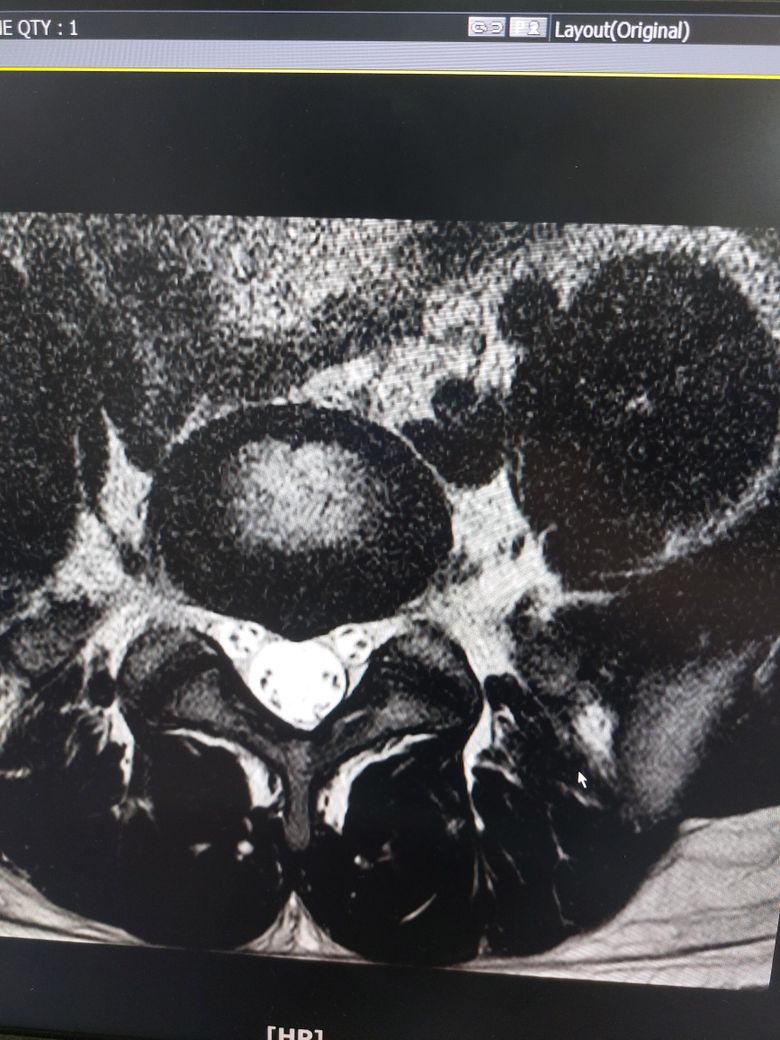

• 4번 째 사진

멸개월전부터 요추가 뻣뻣하고 시큰거리다가 최근에 좀 나아지긴 해도 만성적이라서 오늘 mri 찍고 허리디스크 진단받았습니다

(요추 맨 밑 천추 위 디스크)

신경이 심하게 눌리고 있지는 않은 것으로 보입니다. 충분히 휴식하여 주시고, 허리에 무리가 많이가는 자세는 당분간은 피해주시는 것이 좋습니다.